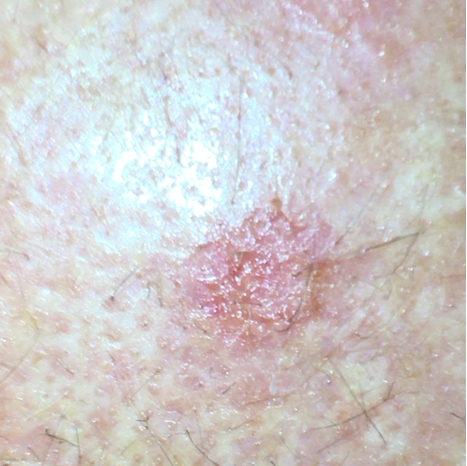

Příklad aktinické keratózy

Aktinická keratóza má často barvu kůže až červenohnědou a má vyvýšená místa a drsný, krustovitý povrch. Doslovný překlad slova „aktinická keratóza“ totiž znamená „zrohovatění kůže způsobené sluncem“. Krusta má často bílou barvu, ale může mít i žlutou nebo hnědou. Skvrny mají často velikost několik milimetrů až centimetrů. Obvykle se neprojevují žádnými příznaky, někdy se objevuje nepříjemný pocit nebo svědění. Tato kožní abnormalita se často nachází na obličeji, hřbetu rukou, paži, noze, dekoltu, ušním boltci nebo u plešatících mužů na pokožce hlavy. Obvykle se na kůži vyskytuje větší počet AK.